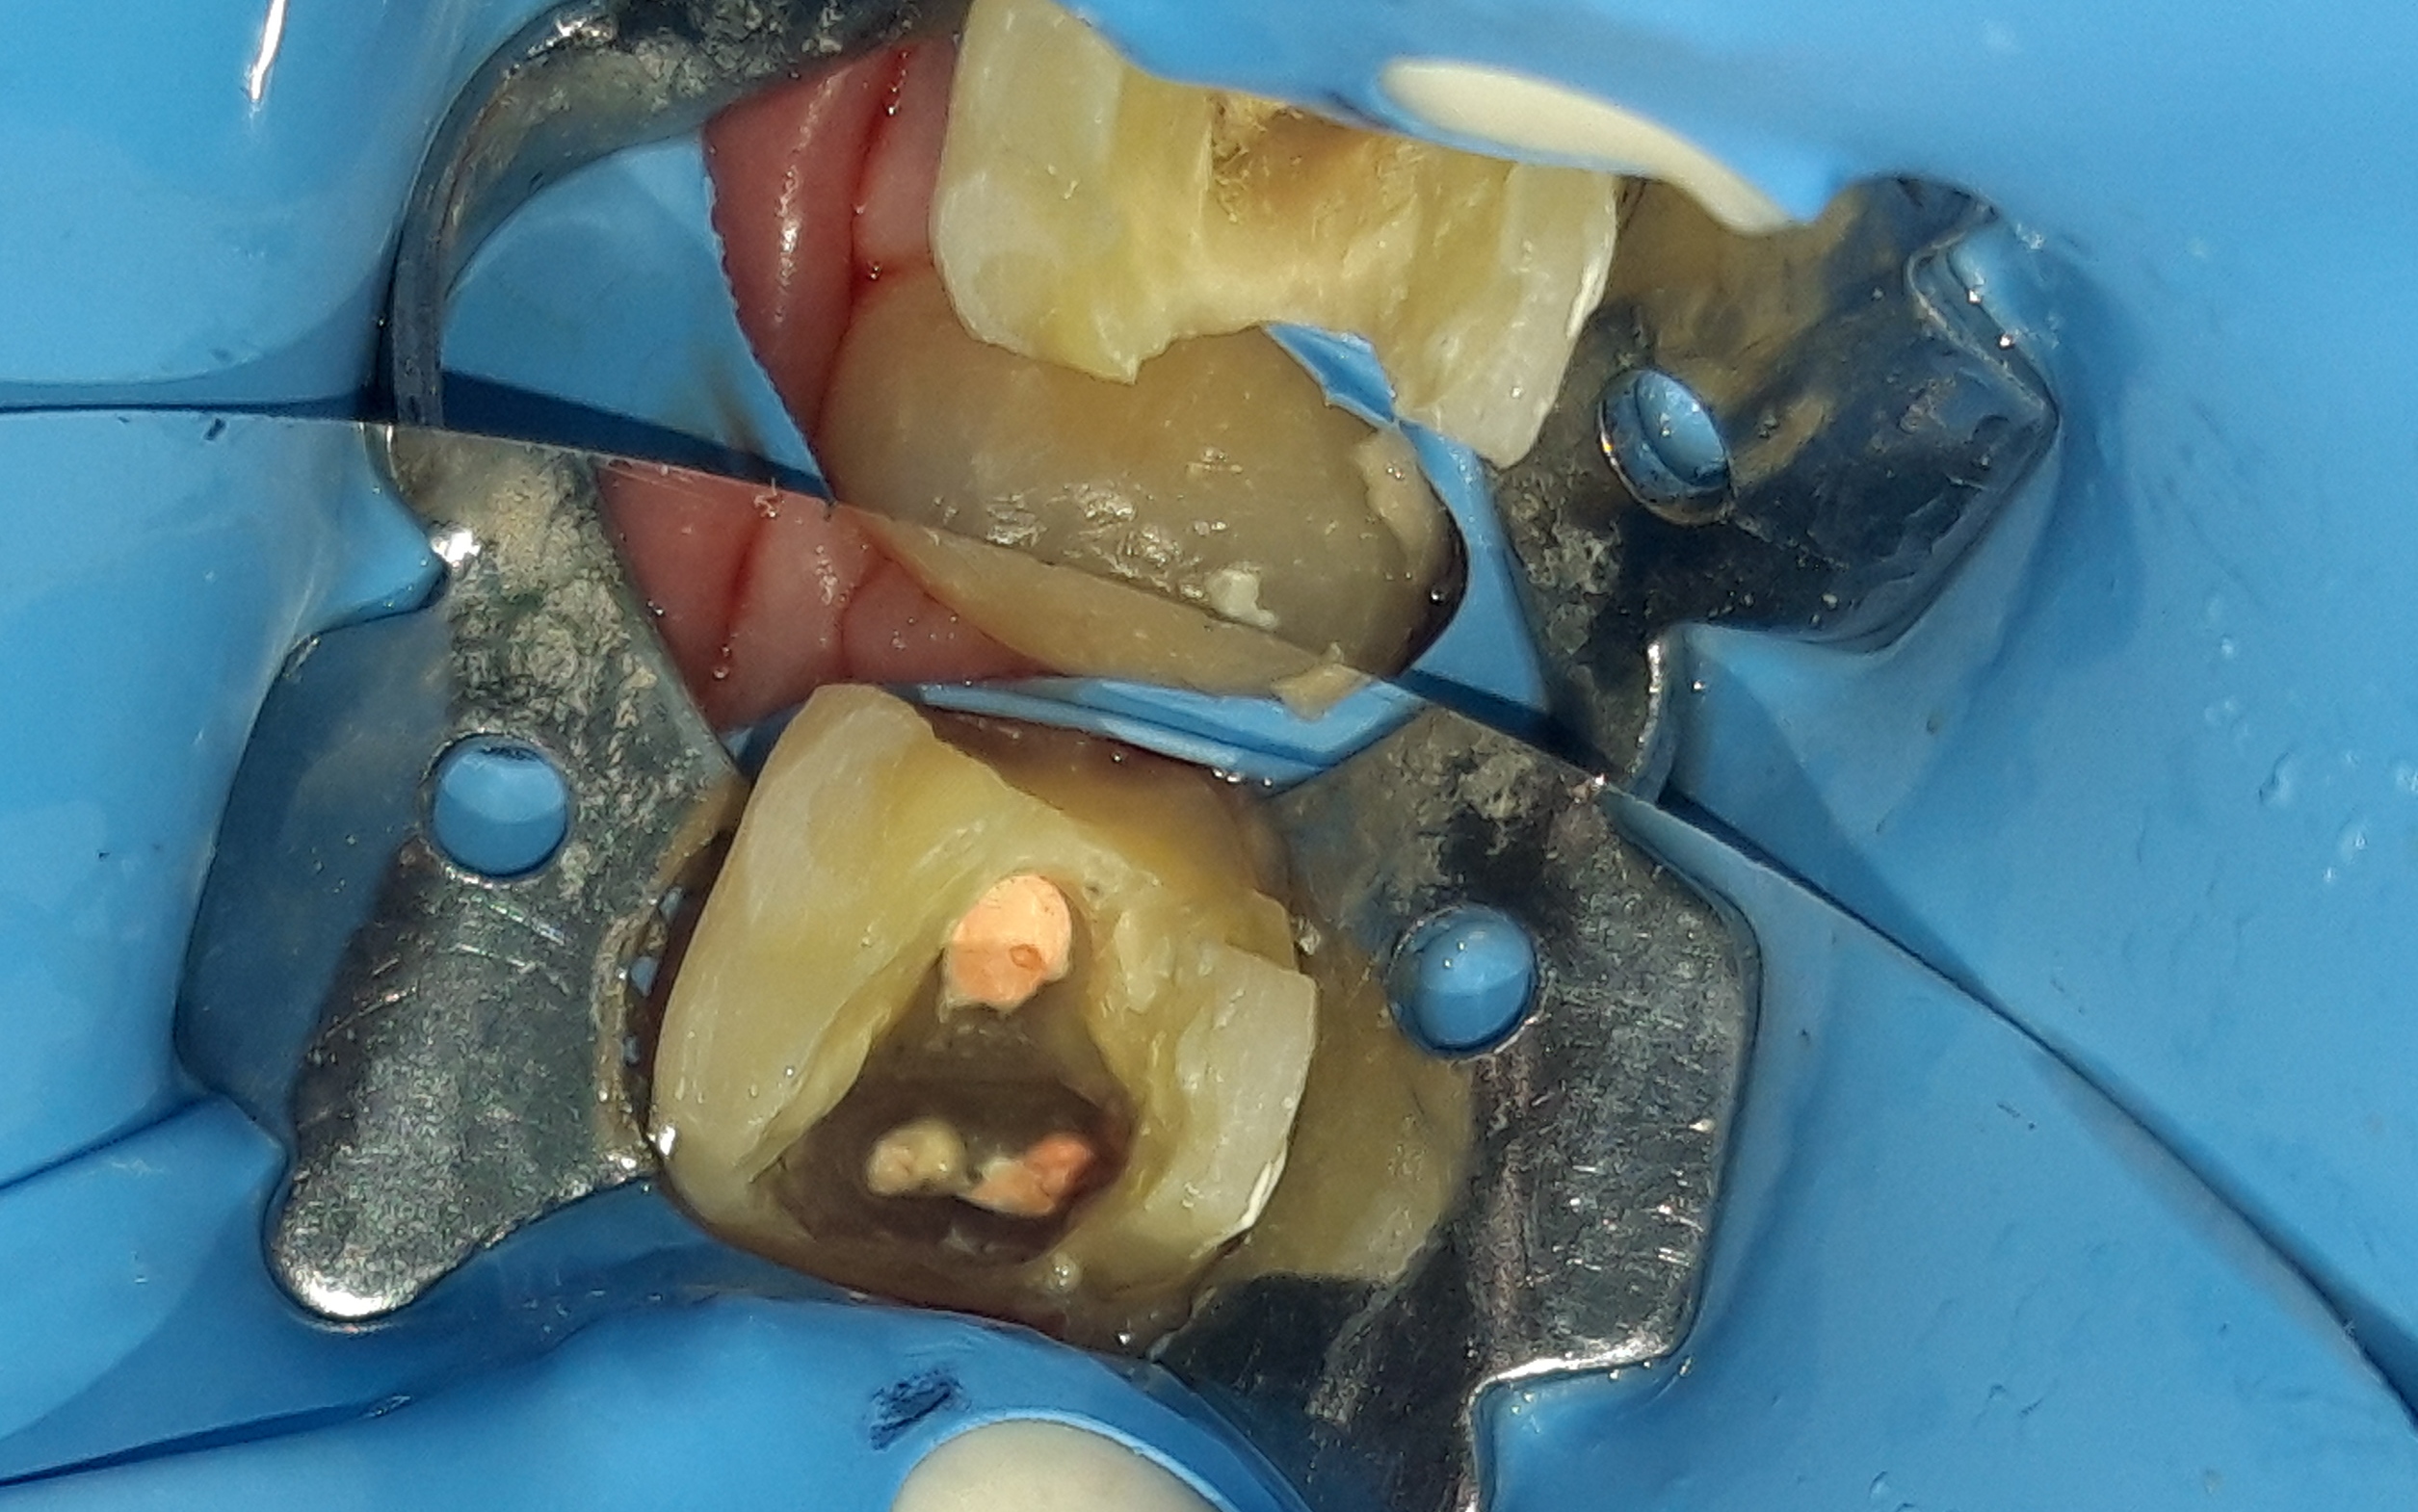

Περιστατικό – Ολοκεραμικό επένθετο ζιρκονίου στον άνω αριστερό γομφίο

Στη συγκεκριμένη ασθενή πραγματοποιήθηκε απονεύρωση δοντιού. Το οδοντικό έλλειμμα ήταν μεγάλο, οπότε το δόντι μετά την απονεύρωση έπρεπε να αποκατασταθεί είτε με θήκη δοντιού είτε με ολοκεραμικό ένθετο. Τελικά αποφασίστηκε η αποκατάσταση με ένθετο δοντιού, γιατί χρειάστηκε να θυσιαστεί λιγότερη οδοντική ουσία. Η ασθενής είναι ευχαριστημένη τόσο με τη λειτουργικότητα όσο και με το αισθητικό αποτέλεσμα.

Αρχική κλινική εικόνα του μεγάλου οδοντικού ελλείμματος